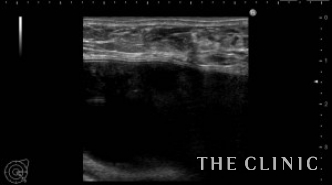

他院にてヒアルロン酸豊胸・バッグ豊胸を受けられ、その直後からしこりが触れはじめたとのこと。豊胸を受けたクリニックでは取り合ってもらえず、更に他院へ相談するがバッグが入っているため処置は難しいと言われ、当院を受診されました。 しこりの大きさは1cmですが、被膜を形成しています。

ヒアルロン酸のしこりのすぐ下にシリコンバッグ がありますのでバッグを損傷しないように注意する必要があります。 エコー下にて確実にヒアルロニダーゼをしこり内に注入し、その後ヒアルロン酸を吸引除去します。